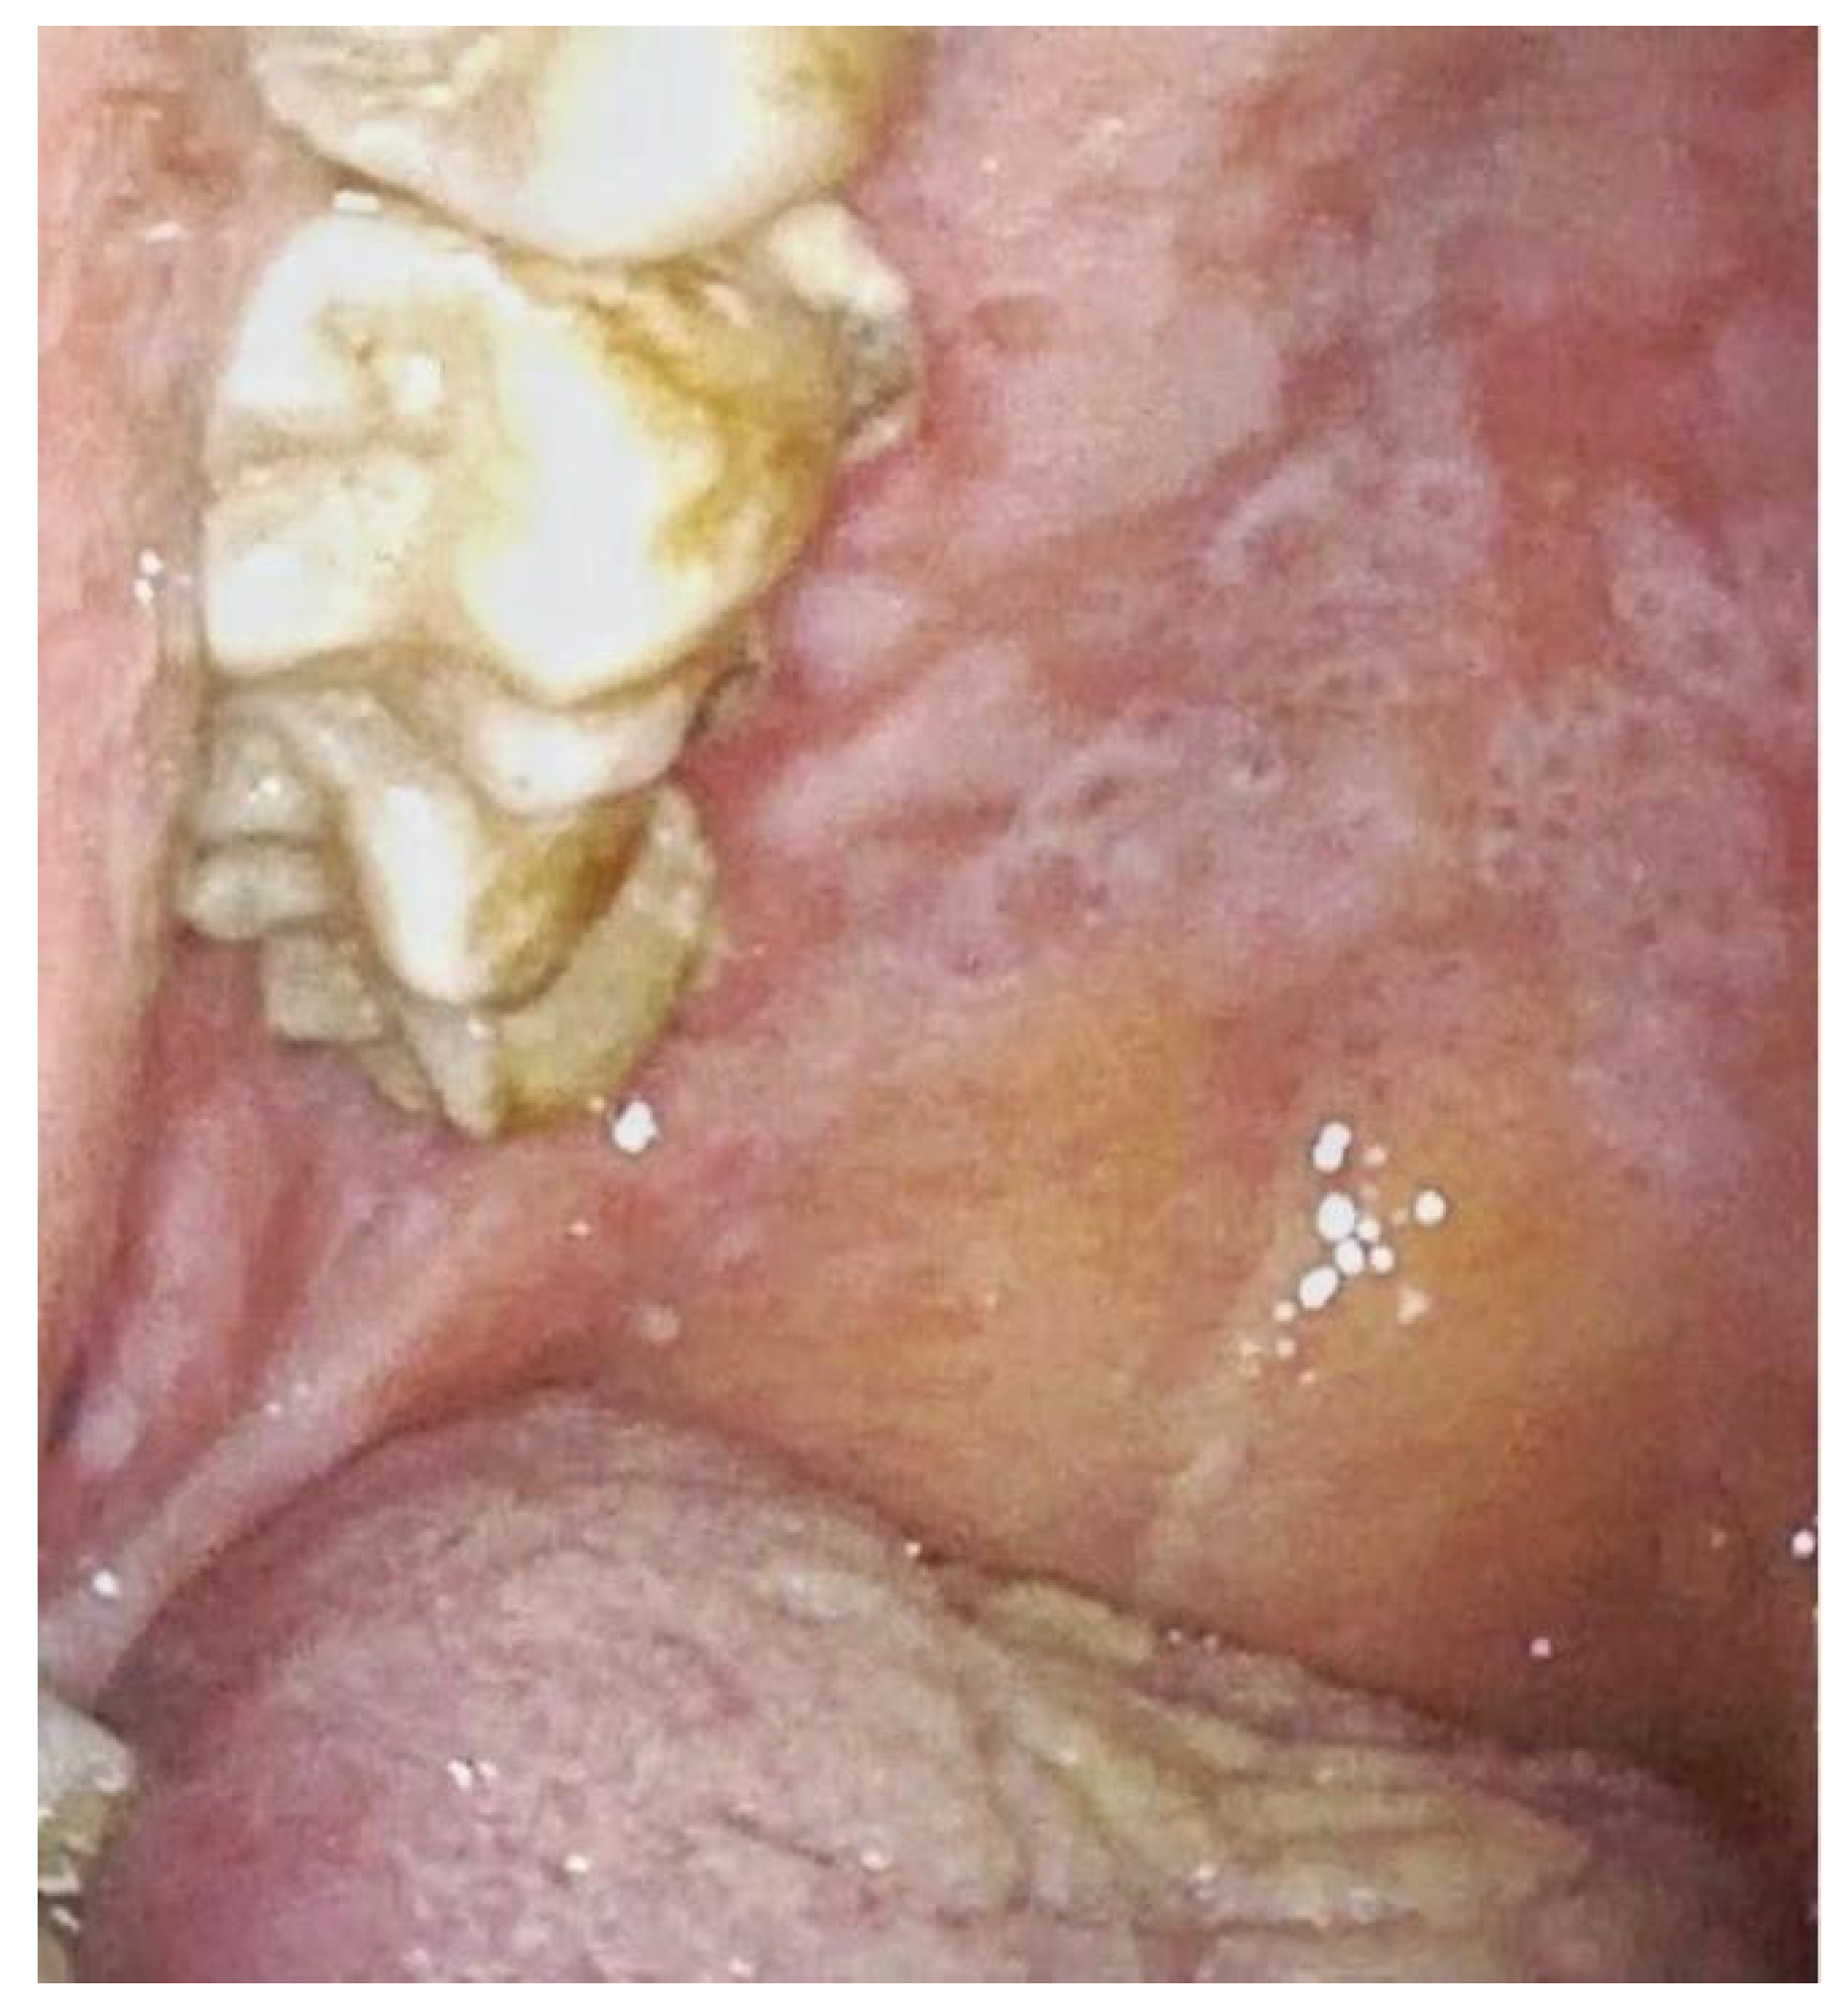

| 2 | Buccal mucosa bilaterally and left tonsillar pillar with extension at amygdalo-glossus sulcus and oropharynx | Erythroplakia paired with central erosive area | Diffuse mucositis and evidence of erythroplakia with erosive central area suspicious for malignant disease | Evidence of intrapapillary capillary loops | Squamocellular carcinoma of the oropharynx. |

| 3 | Right buccal mucosa and lateral right surface of the tongue. | Leukoplakia of the right surface of the tongue with an indurated area in the lower portion. | Reticular lichenoid-like lesions on the right buccal mucosa without suspicious of malignancy | Evidence of intrapapillary capillary loops. | Epitelial verrucous hyperplasia |